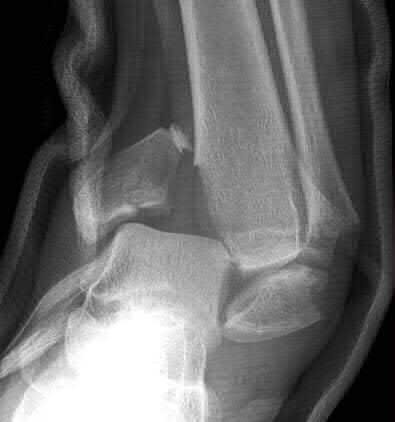

A 28-year-old male sustains a severe hyper-dorsiflexion injury to his ankle in a motor vehicle accident, resulting in a Hawkins Type III talar neck fracture. Which of the following arteries provides the predominant blood supply to the body of the talus, placing it at significant risk for avascular necrosis in this injury?

Options:

Correct Answer: Artery of the tarsal canal

Explanation:

The artery of the tarsal canal, which is a branch of the posterior tibial artery, provides the dominant blood supply to the talar body. In a Hawkins Type III fracture (talar neck fracture with subtalar and tibiotalar dislocation), the blood supply from the artery of the tarsal canal, the artery of the sinus tarsi, and capsular vessels are disrupted, leading to an avascular necrosis (AVN) rate approaching 100%.